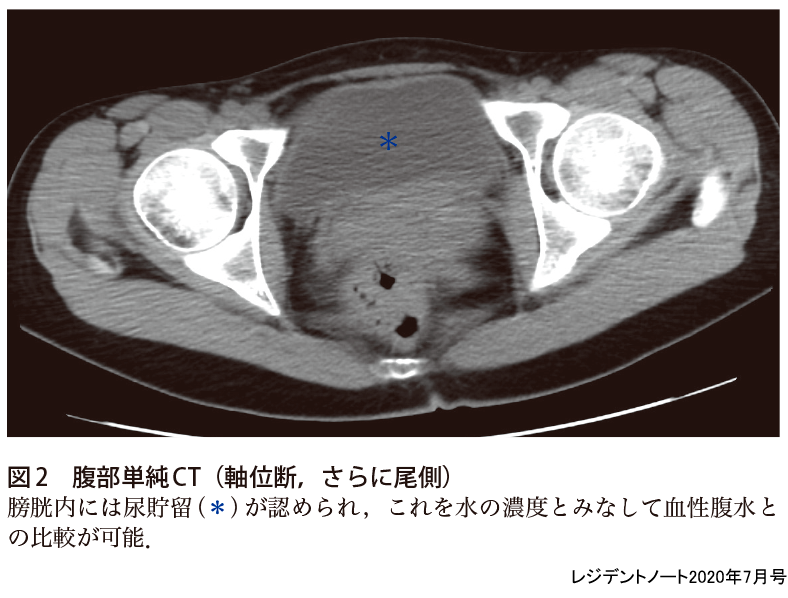

犬 腹水 画像-画像を中心に(腹部編) KKawashima 19年2月19日 引き続き画像関連について、腹部を中心にピックアップします。 だーっと書いたので、まとまっていませんが宜しくお願い致します。 直前で申し訳ありません。 画像引用:長尾大志,レジデントのためのやさしイイ胸部画像教室,p81 立位では、肺の下のほうに胸水が溜まるので (液体は下のほうにたまり) 、CP angle dullとなってわかります。 ただし、少量の胸水の発見には、正面のレントゲン画像はあまり役に立ち